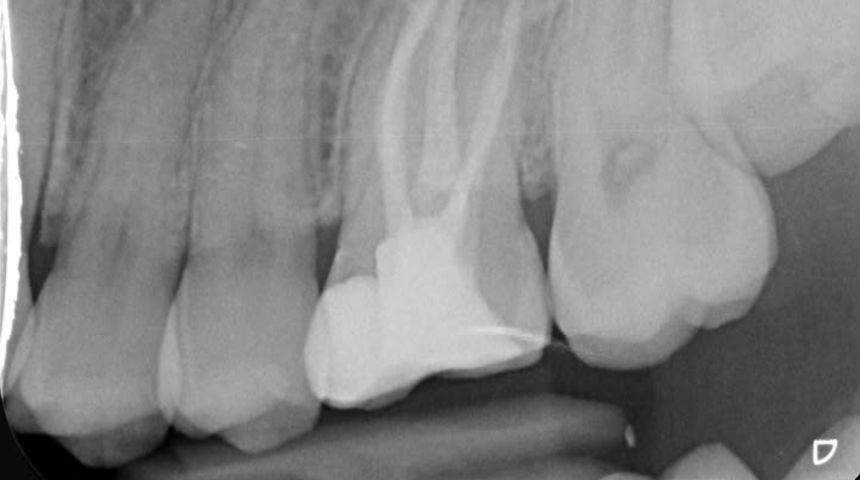

Take a look at some of our recent cases below!